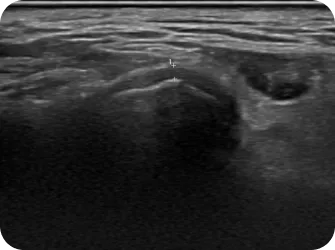

턱관절 디스크 및 연조직 초음파

디스크 두께 파악